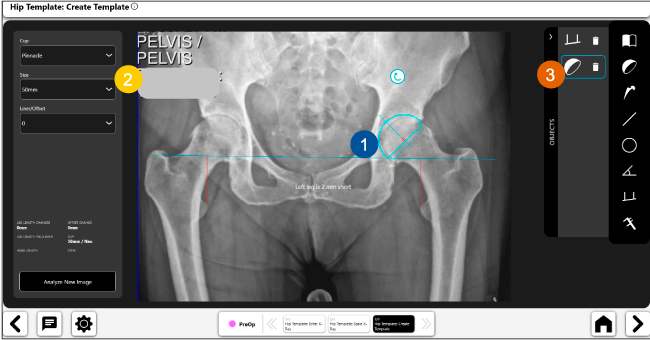

Planeación preoperatoria mediante la creación de plantillas digitales para reemplazo de cadera y análisis intraoperatorio

Disponibilidad de plantillas digitales de cadera.

Expediente histórico y personalizado, optimiza la planeación con el calendario de casos realizados en Velys TM y utiliza los íconos interactivos para una rápida revisión.

Espacio colaborativo: puede compartir los casos entre cirujanos y sus equipos mediante la funcionalidad de intercambio de información.

Mayor nivel de información intraoperatoria facilita la colocación correcta de los implantes:

Inclinación y anteversión de la copa acetabular para una correcta colocación del implante.

Anotaciones digitales y herramientas de análisis de longitud de pierna.